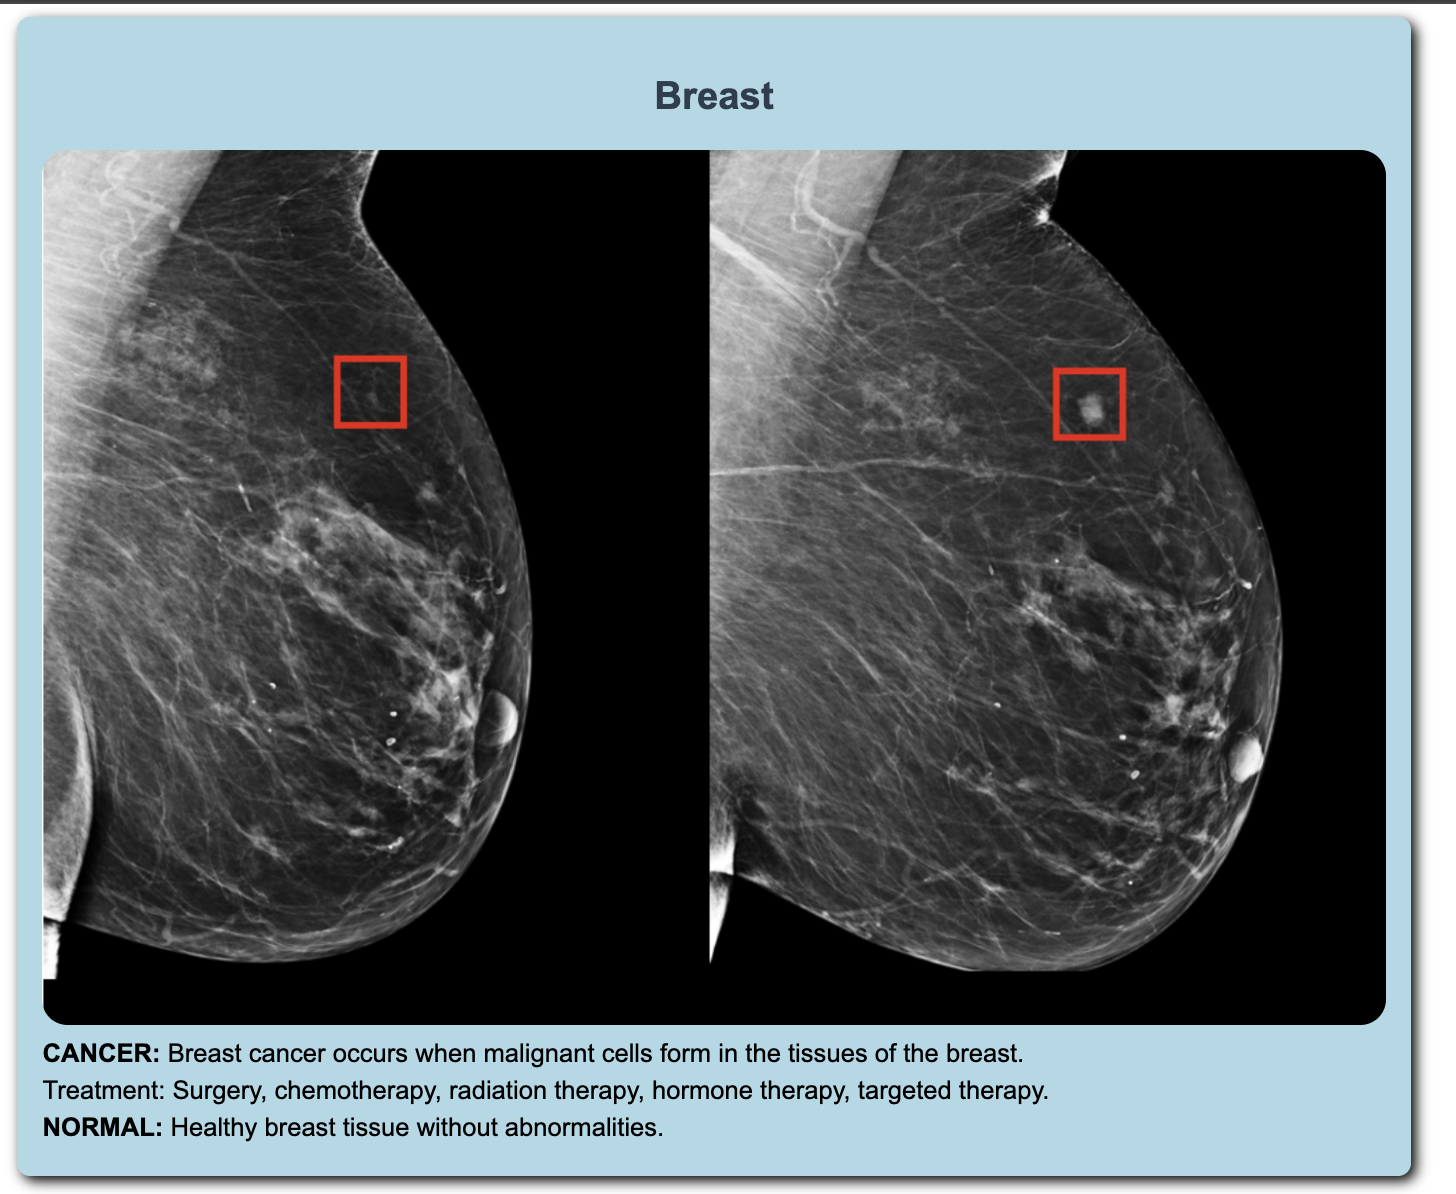

The AI-Powered MediKit enhances medical analysis with several advanced features. Most of its functionalities are classification-based, but instead of relying on conventional CNNs, we've incorporated Vision Transformers (ViTs) for model training. While CNNs and CNN-based networks like ResNet excel in detecting simple features, they struggle with the subtle details often present in medical images. Vision Transformers, however, excel at capturing these delicate features. Additionally, the MediKit offers Heartbeat Analysis using MFCC to classify heartbeats, which helps in identifying abnormalities. We also provide few-shot classification for tablets, minimizing the need for retraining the network with new data. The project includes a herbal solution feature where users can inquire about herbal remedies.